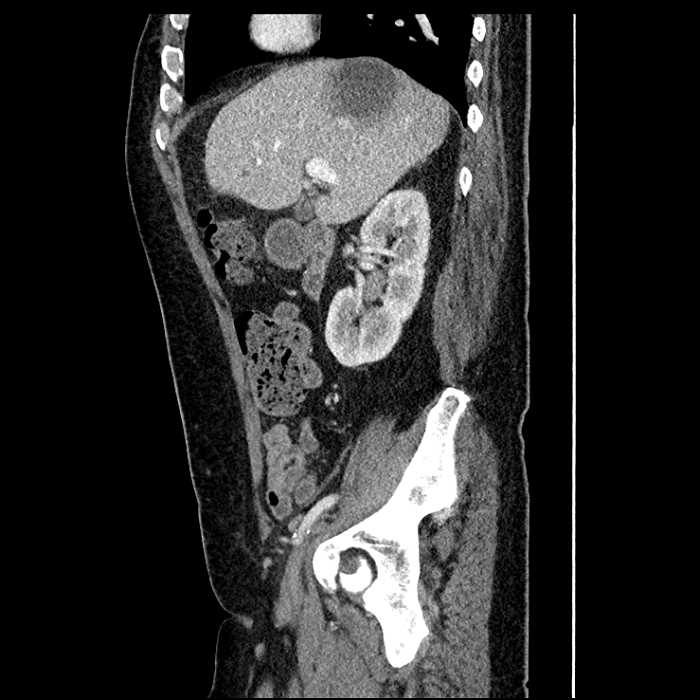

Acute sigmoid diverticulitis complicated by a small contained perforation and a large abscess in the right hepatic lobe. Additional small subcapsular abscesses along the anterior margin of the left hepatic lobe.

• The classic CT imaging appearance is a double target sign with internal low density surrounded by an internal enhancing rim (capsule) and a low density external rim (edema)

Hepatic abscess showing the double target sign with low density internally surrounded by a thin inner enhancing rim (red arrow) and ill-defined outer low density rim (yellow arrow). Blue arrow indicates an internal septation. Red arrows: additional smaller subcapsular abscesses. Red arrow: focal contained perforation associated with diverticulitis.